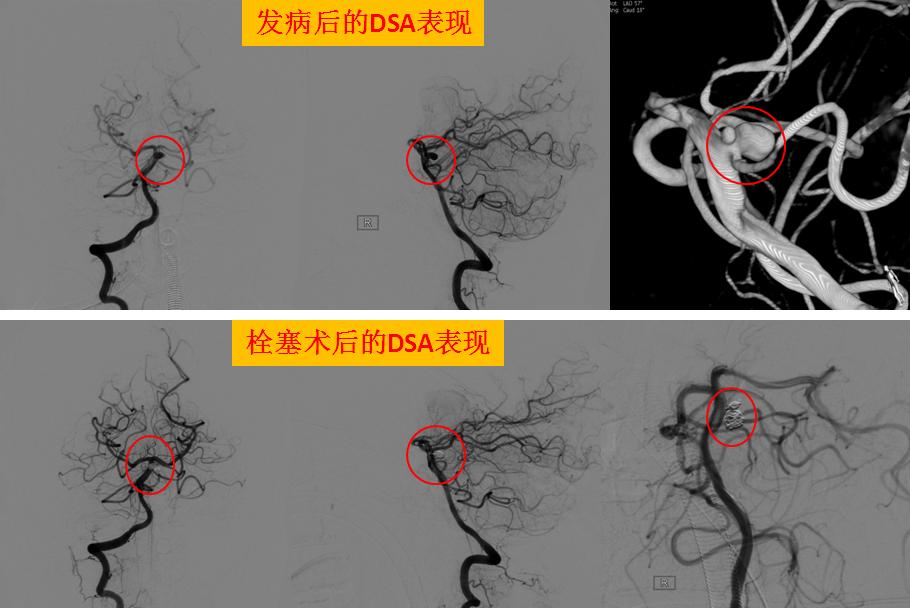

患者郑某在家中突发昏迷不醒,由120救护车送入我院救治,我院神经外科立即启动卒中绿色通道,行头颅CT和DSA脑血管造影提示:脑内动脉瘤破裂伴蛛网膜下腔出血。因脑内动脉瘤随时都有可能再破裂,引起脑出血,此时情况十分危险!在征得患者家属同意后,神经外科团队为郑某实施脑内动脉瘤介入治疗,用弹簧圈栓塞动脉瘤,经过3个小时的努力,弹簧圈被顺利放入动脉瘤腔处,将动脉瘤与正常血管完全隔离,达到防止再出血的效果,手术成功!

这次对患者实施的DSA全脑血管造影+脑内动脉瘤弹簧圈介入栓塞术是神经介入治疗的一种方式,手术利用现代影像技术把弹簧圈填充到动脉瘤腔里,让血液无法进入,达到避免脑出血的目的。该介入治疗具有创伤小,恢复快,痛苦小等优点,是目前介入治疗脑动脉瘤的首选方法。